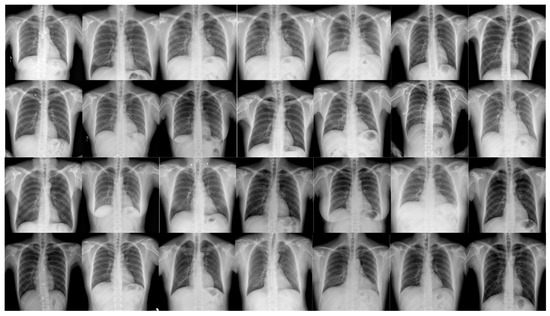

X-ray images of pneumonia typically exhibit complexity, diversity, and low contrast, necessitating the construction of an efficient and accurate pneumonia X-ray image dataset [13,14,15]. We used the open-source MIMIC Chest X-ray pneumonia dataset; the images were re-annotated using the LabelImg tool (as detailed in Table 1), which includes annotations for five categories: bacterial pneumonia, viral pneumonia, illness, healthy, and tuberculosis.

In this paper, we propose a targeted online data augmentation method. This method integrates several advanced image enhancement techniques, including Mixup and Mosaic, for comprehensive dataset preprocessing, significantly improving the model’s generalization ability and robustness [16,17,18,19].Annotated examples from the pneumonia dataset are shown in Figure 1. Specifically, the data augmentation process involved HSV transformation, translation, scaling, horizontal flipping, random cropping, zooming, and stitching [20,21]. These techniques not only effectively increase the sample size but also enhance the model’s sensitivity and adaptability in small-object detection, providing strong support for the overall optimization of model performance.

Figure 1. Pneumonia detection dataset.